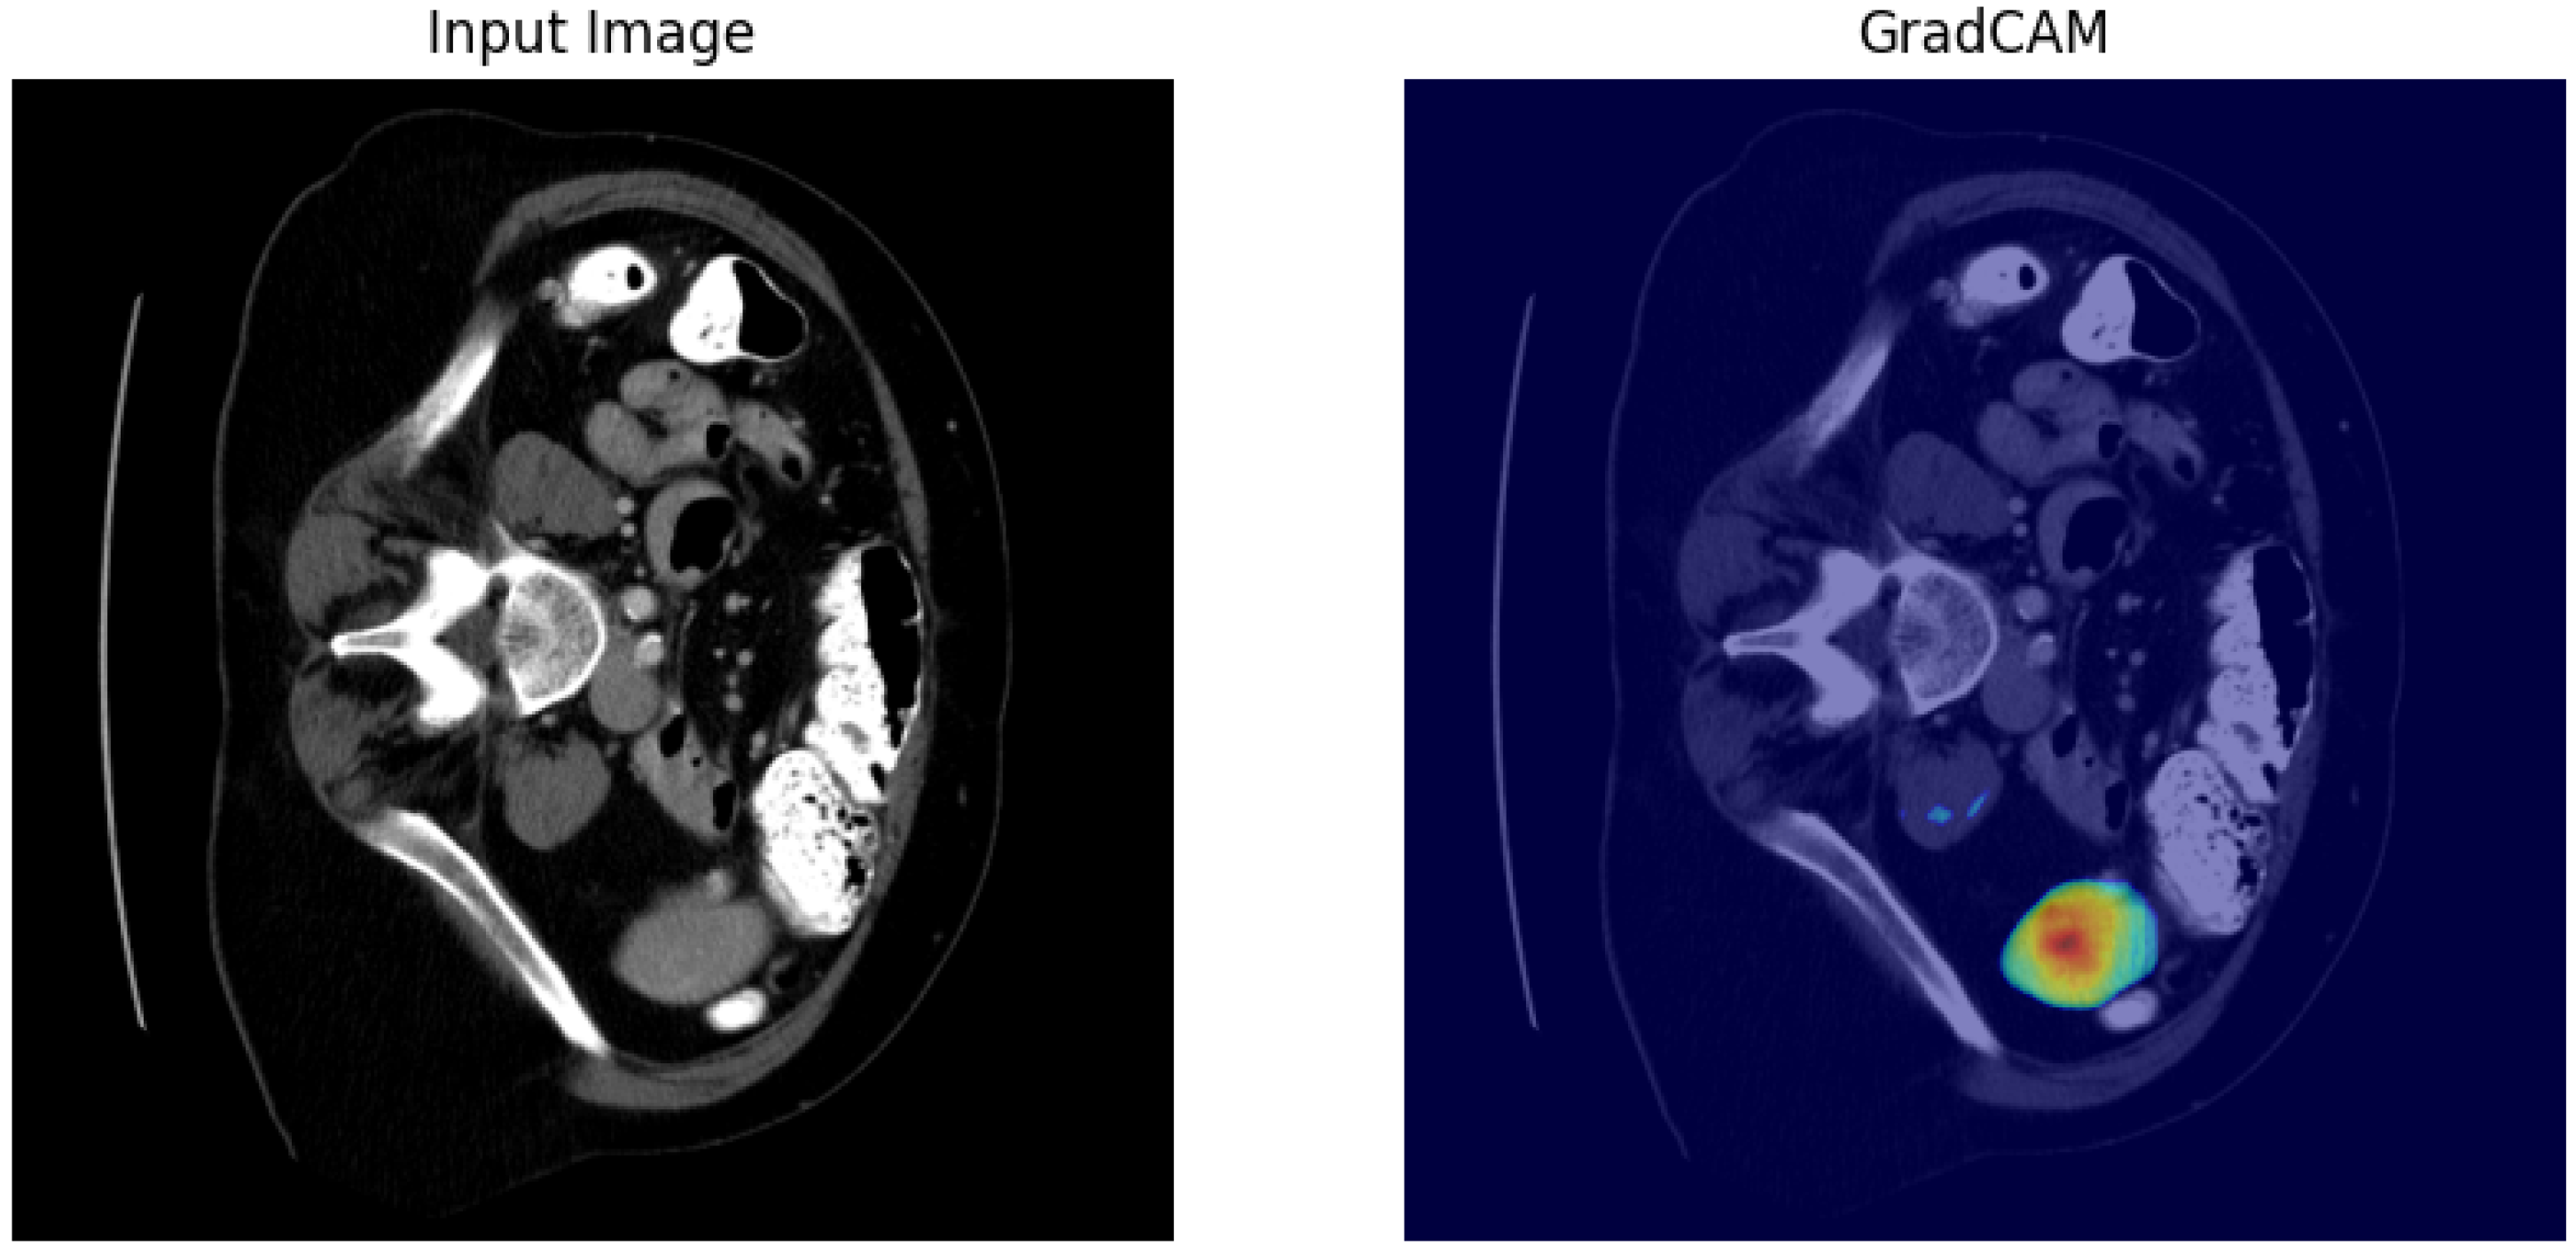

Enhanced U-Net for Spleen Segmentation in CT Scans: Integrating Multi-Slice Context and Grad-CAM Interpretability

- Selvaraju, R.R.; Cogswell, M.; Das, A.; Vedantam, R.; Parikh, D.; Batra, D. Grad-CAM: Visual explanations from deep networks via gradient-based localization. In Proceedings of the IEEE International Conference on Computer Vision, Venice, Italy, 22–29 October 2017; pp. 618–626. [Google Scholar] [CrossRef]